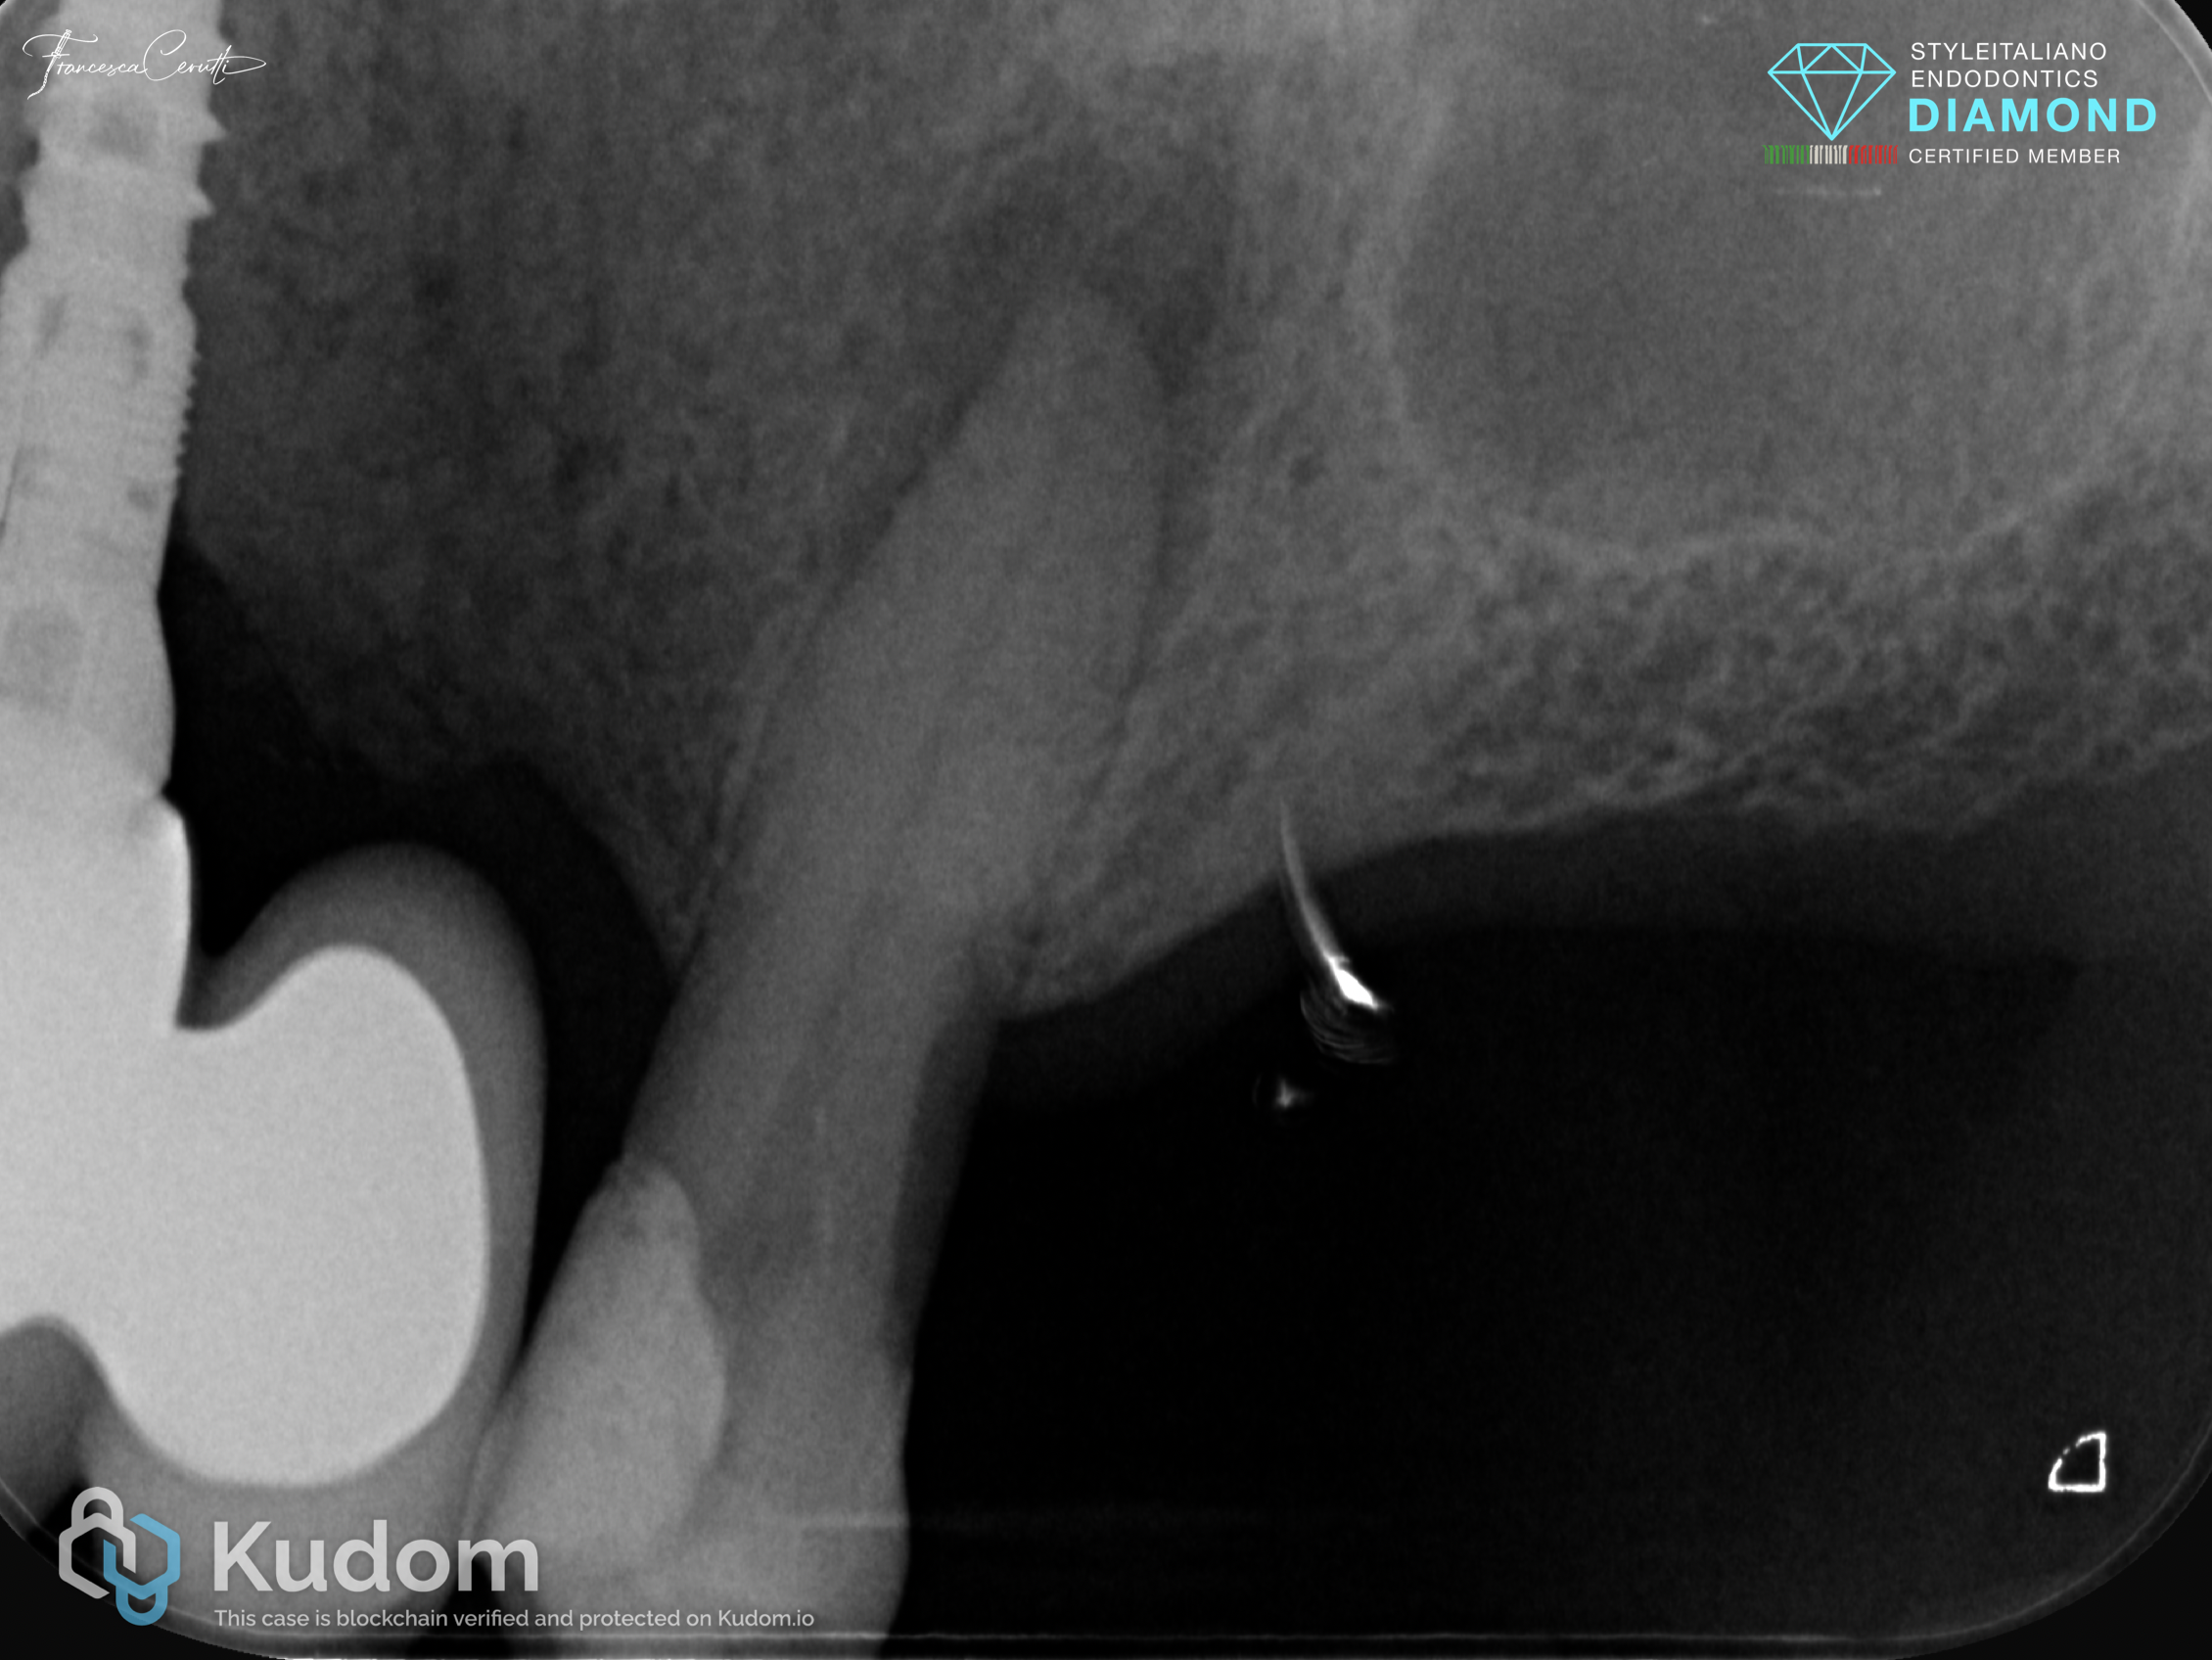

Fig. 1

A patient came to my attention complaining of pain to percussion on tooth 2.5. A large restoration was present. The periodontal status of the tooth was normal, without deep probing, and the tooth was not responding to pulp sensibility tests.

The pre operative X-ray showed the presence of a large lesion, thus the diagnosis of symtpomatic apical periodontitis in a tooth with necrotic pulp was easily made.